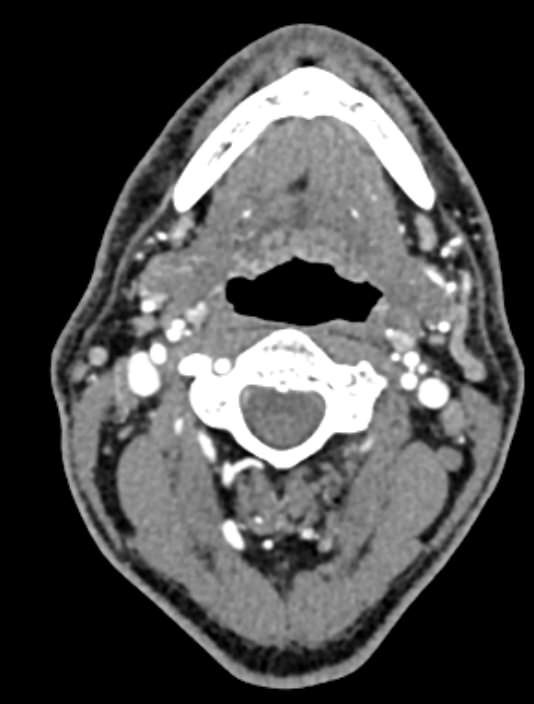

КТ сосудов шеи и головного мозга (КТ-ангиография) позволяет комплексно оценить состояние брахиоцефальных артерий и сосудов головного мозга, включая Виллизиев круг, передние средние и задние мозговые артерии. С помощью КТ-ангиографии можно выявить аномалии развития сосудов (в том числе, аневризмы артерий головного мозга, артериовенозные мальформации), патологические извитости, участки сужения и полной закупорки просвета сосуда. КТ-ангиография покажет утолщение стенки артерии, точную локализацию атеросклеротической бляшки, стенозы и окклюзии просвета сосудов, степень функционирования Виллизиева круга, что бывает особенно важно при планировании оперативного вмешательства и для оценки эффективности хирургического лечения.

В нашей клинике КТ сосудов шеи и головного мозга выполняется на современных мультиспиральных компьютерных томографах экспертного уровня TOSHIBA AQUILION. Для визуализации сосудистой системы в обязательном порядке проводится контрастное усиление. Для этого в вену пациенту вводится йодсодержащий контрастный препарат, который хорошо поглощает рентгеновские лучи и обеспечивает яркую видимость сосудистой сети на фоне окружающих тканей.

Высокотехнологичное оборудование последнего поколения обеспечивает высокую точность и контрастность изображений, благодаря чему получаются снимки и трехмерные модели сосудистой системы высокого качества. Увеличенное количество детекторов позволяет производить одномоментно множество послойных снимков, что значительно сокращает время исследования и минимизирует уровень лучевой нагрузки на организм пациента.